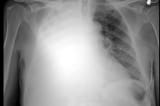

Phi công người Anh (BN91) phải can thiệp ECMO vì phổi tổn thương nặng

Bác sĩ tại Bệnh viện nhiệt đới TP.HCM cho biết bệnh nhân 91 có hình ảnh chụp X-quang phổi tổn thương mô kẽ, phế nang lan tỏa 2 phế trường, diễn tiến ngày càng xấu…